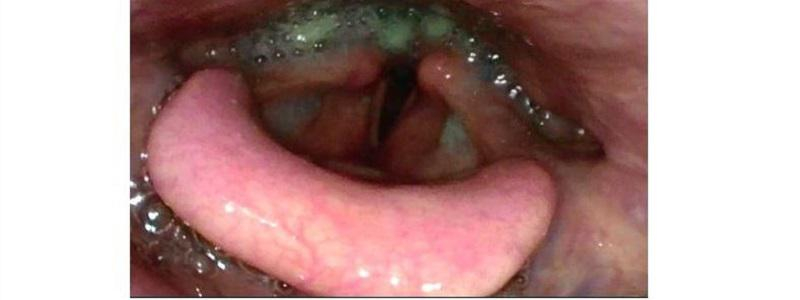

Klinika otorinolaryngologie a chirurgie hlavy a krku Pardubické nemocnice se připojuje k „8. světovému dni polykání“ (8th  World Swallowing Day), který se koná 12. prosince, a nabízí nemocným vyšetření zaměřené na obtíže při polykání. Vyšetření je určeno především pacientům s kašlem při jídle a pití, bolestí při polykání, nebo necíleném hubnutí při obtížném polykání. Vyšetření je zdarma, bez předchozího objednání a proběhne od 8.00 do 12.00 hodin ve všeobecné ORL ambulanci (budova č. 6).

Pacientům bude v indikovaných případech předán kontakt k objednání do specializované poradny pro poruchy polykání. ORL klinika Pardubické nemocnice se poruchami polykání a zejména speciálními vyšetřeními zabývá od roku 2007. Je prvním pracovištěm v České republice, které začalo s využitím flexibilní endoskopie k diagnostice a ve spolupráci s klinickým logopedem i k terapii poruch polykání (Flexible Endoscopic Evaluation of Swallowing - FEES). Převzala a do praxe uvedla v zahraničí využívanou metodiku vyšetření pomocí barevně odlišené stravy různé konzistence.

Dále se ve spolupráci s radiodiagnostickým pracovištěm rozvinulo provádění videofluoroskopie (vyšetření polykání kontrastní látky pomocí RTG přístroje). Za celou dobu více než desetiletého úspěšného fungování poradny pro poruchy polykání byly vyšetřeny stovky pacientů. Řadě pacientů bylo možno s polykáním pomoci a významně tak zvýšit kvalitu jejich života. MUDr. Iva Bártová, zástupce primáře, vedoucí lékař poradny pro poruchy polykání Mgr. Renata Coufalová, klinický logoped